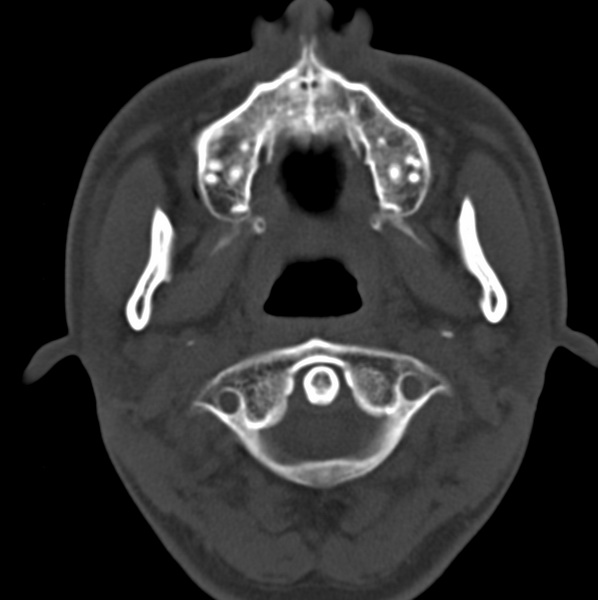

男、31、鼻咽部肿瘤放疗后请帮忙看看。

效果好,右侧破裂孔扩大,局部骨质缺损,为颅底骨质破坏。

1)鼻咽部肿瘤侵犯颅底放疗术后改变。2)左侧蝶窦炎。

咽后壁增厚,左侧咽鼓管隆突增大、咽鼓管咽口变浅,同侧咽旁间隙较窄。右侧颅底骨质破坏?为什么不在同一侧?

鼻咽部肿瘤侵犯颅底放疗术后改变.